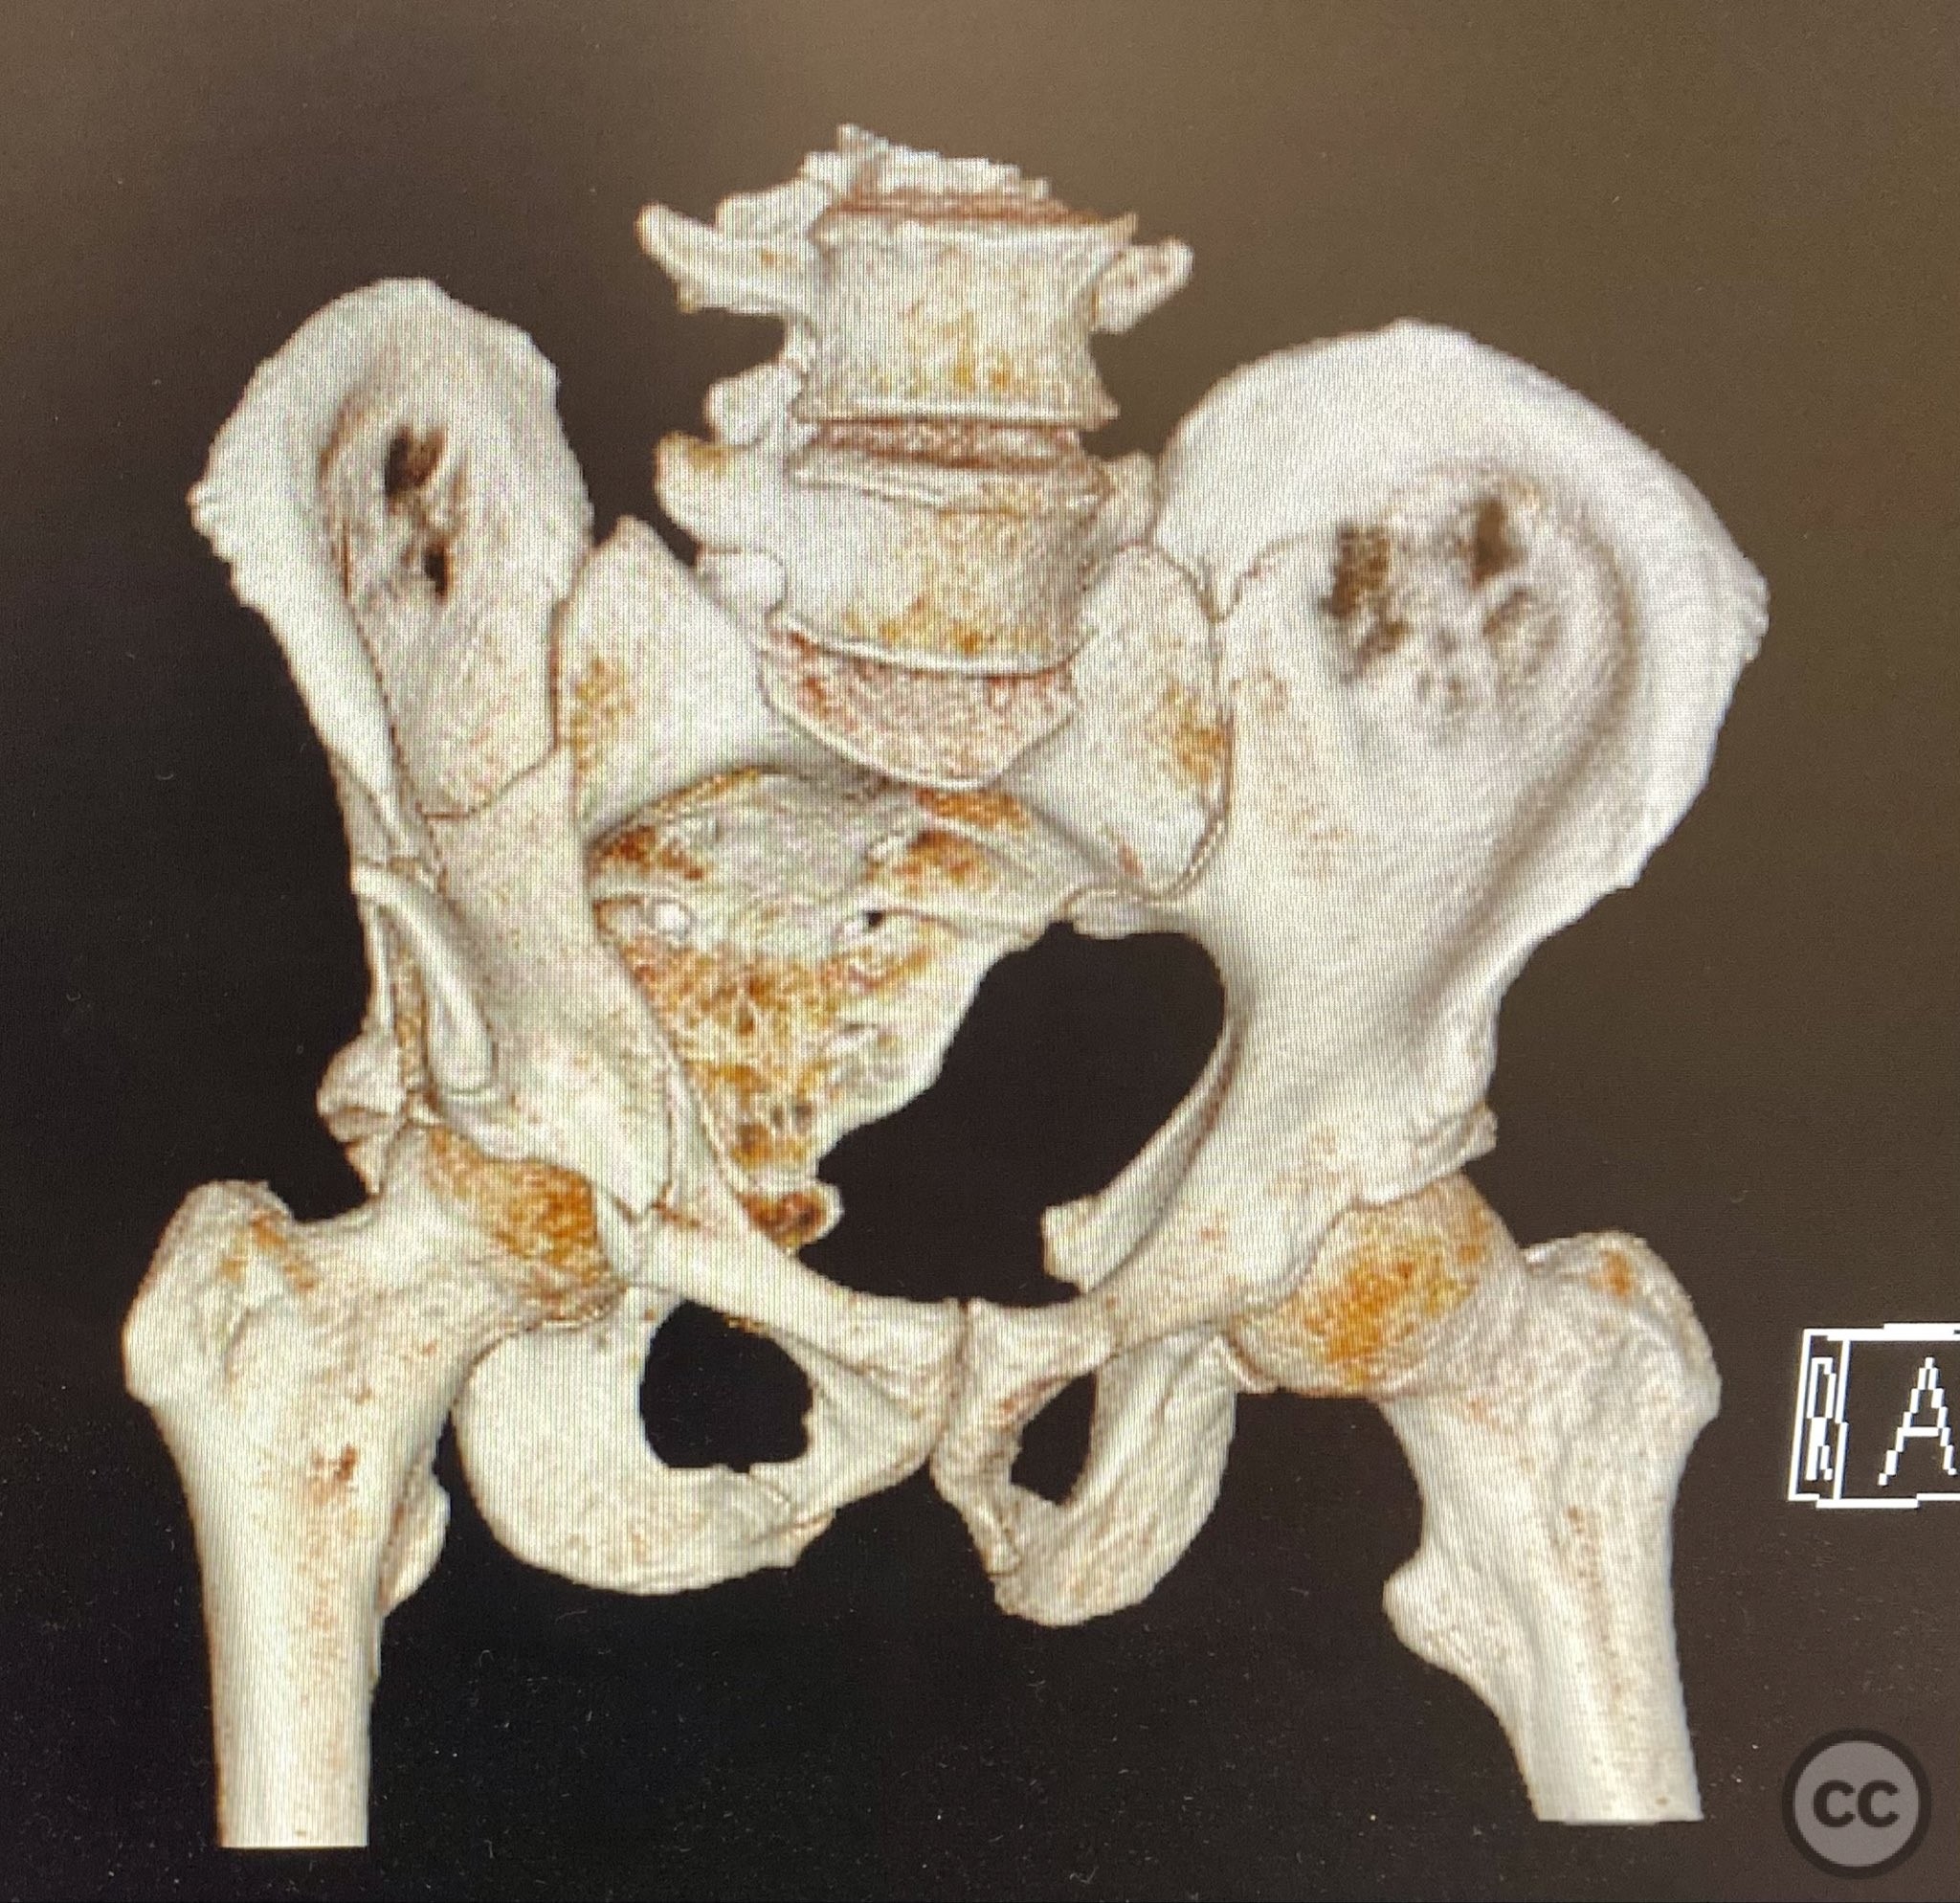

Clinical and radiological findings:  A patient presented with a combined anterior column and posterior hemi-transverse (AC/PHTr) acetabular fracture. Plain radiographs demonstrated multiple displaced fragments involving the acetabular dome and femoral head region, with clear disruption of the anterior column and posterior transverse components. Advanced imaging, including axial and coronal CT, provided detailed visualization of cortical surface displacement, fragment orientation, and associated soft tissue status. The edge of the intact dome and femoral head injuries were identified, as well as a residual defect at the edge of the dome following reduction. AO/OTA classification: 62B2 (anterior column with posterior hemitransverse).

Surface renderings from preoperative imaging facilitated intraoperative correlation between radiographic and fluoroscopic views, aiding in precise interpretation of fragment orientation during reduction. The use of focal plates allowed for maintenance of provisional reductions with bone holding clamps during definitive fixation. Restoration of radiographic lines was confirmed on intraoperative AP fluoroscopy, while postoperative axial CT demonstrated successful central dome repair with a residual edge crush defect at the dome margin.